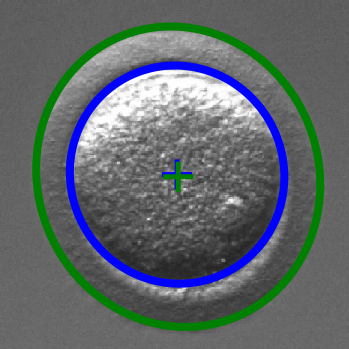

Infertility is becoming an issue for an increasing number of couples. The most common solution, in vitro fertilization, requires embryologists to carefully examine light microscopy images of human oocytes to determine their developmental potential. We propose an automatic system to improve the speed, repeatability, and accuracy of this process. We first localize individual oocytes and identify their principal components using CNN (U-Net) segmentation. Next, we calculate several descriptors based on geometry and texture. The final step is an SVM classifier. Both the segmentation and classification training is based on expert annotations. The presented approach leads to a classification accuracy of 70%.